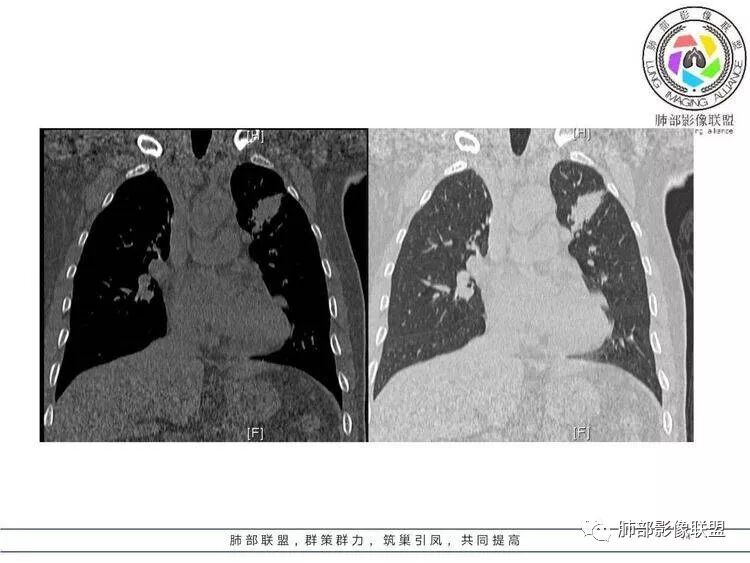

王秀仙:左肺上叶肿块,边缘平直收缩,周围可见长索条,轻度强化,密度不均可见低密度坏死,考虑结核。鉴别腺癌。Yiren  Sishui(厶水伊人):晨读:左肺上叶肿块,近胸膜侧光滑,提示符合淋巴回流病变,周围条索,符合肉芽肿性病变,环形强化,中心坏死,考虑结核可能luys:左肺上叶病变,沿支气管分布,边缘平直收缩,周围见长索条,轻度强化,伴边界可见低密度坏死灶。考虑特殊感染。灶内支气管中断,临床以咯血就诊,鉴别肿瘤。博麟:左上胸廓稍缩小,长条索病灶,冠状位似见支气管截断,坏死边界似乎欠清,猜个纤维条索基础上合并瘢痕癌红日东升:晨读:左上叶结块,前缘有粗大索条向前延伸,邻近前联合线明显左移,提示收缩明显。结块边缘平直、收缩;增强结块及索条明显强化,内血管走行自然,坏死灶周围似见三层结构;考虑炎性病变。wonderful:肿块实性边缘光滑  考虑良性病变 合并咯血 。结核或曲霉玫:左肺上叶不规则形软组织密度肿块影,边界清晰,期内密度不均匀,可见坏死,病灶向前呈条索状延伸,矢状位病灶形态欠规整,似有血管中断,考虑恶性病变可能,待除外结核?张帅:左肺上叶病变,病变周围平直,长毛刺,病灶内可见低密度区及支气管征,矢状位提示前段阻塞,病灶内气管不规则扩张,病灶周围有卫星灶,考虑良性病变:结核?我心飞翔:病灶边缘平直,中央可见坏死,周围磨玻璃边界欠清,考虑炎性病变张延军:左肺上叶尖后段肿块,边缘以平直为主,局部膨隆,内见片状坏死区,边界欠清,相应尖后段支气管闭塞,考虑占位并不张,腺癌?建议抗炎治疗后复查丽:左肺上叶病变,边缘平直,并可见长索条,增强后密度不均,可见坏死,首先考虑结核,但重建后支气管走形欠连续,似有截断,恶性待排毛勤香:左肺上叶病灶,边缘平直为主,周围索片影,增强强化不均匀,内有坏死,重建支气管走行欠规则,似有截断,老年男性,需排除恶性(鳞癌?)并阻塞性肺炎可能王萍:左肺上叶团片,大部分边缘平直、凹陷,周围见少许条片模糊影,增强内见坏死区,余区域较均质,其内支气管部分通畅,部分变窄。咯血病史,无发热,考虑肉芽肿性炎可能性大,结核或放线菌等,肿瘤待排THINKER:左上叶,占位,围绕尖后段支气管,U型凹丶平直,长索条,有轻强化及低密度,考虑良性的,首选OP,老年不发热丶咯血,鉴鳞癌、TB飞鹰行动:左肺病灶,有明显的收缩表现,增强后病灶内部可见低密度无强化区,病灶内支气管轻度扩张呈串珠状改变,支持炎性病变,结核可能性大。杨泽锋:支持炎性病变伴小脓腔形成,但不支持结核,因为病灶内可以可见血管影THINKER:问一下各位老师:这个给的强化,是肺动末期丶主动脉未期`延迟期?大雄:老年男性,左肺上叶前段条片状实变影伴周围长条索,境界清晰,边缘部分锐利光滑、部分毛糙,增强可见中央局部坏死,周围无强化区轻中度均匀强化,无钙化,无明显卫星灶,无胸膜明显牵拉凹陷。病灶整体收缩力有,张力不明显,肿瘤概率小。临床无明显急性感染症状,倾向于慢性增生性炎症,累及段支气管,引起了咯血。结核多见,但慢性结核肉芽肿一般强化没这么明显。OP不除外。老年男性如果有长期吸烟史,鳞癌不能完全排除,鳞癌的坏死强化都符合,鳞癌收缩力也不强,形态更是变化无常左手:老年男性,咯血,左肺上叶长条样结节,边缘见牵拉影,支气管堵塞,病灶内见坏死,坏死边缘偏清,考虑鳞癌,鉴别结核宇宙星空:支持恶性。鳞癌可能性大。支气管截断及空泡征

Shelia:考虑机化性肺炎伴小脓肿形成?炎性肌纤维母细胞瘤?鉴别癌食客:左肺上叶病灶,边缘平直,周围条片影,增强内见坏死区,内支气管部分通畅,咯血病史,无发热,考虑结核,肿瘤不除外。管洪林:左肺上叶尖后段病变,整体边缘平直,部分稍收缩,临近长索条影,胸膜缘可见轻度牵拉,增强后整体强化明显,其内可见低密度类圆形坏死区,边界清,首先考虑op并小脓肿形成,但部分层面显示小支气管受阻,是否层面原因?管洪林:若是支气管阻塞,鳞癌作为鉴别雪上一枝蒿(陈显静):他这个动脉期是不是不是很明显啊,觉得跟静脉期差不多,强化值也不好分辨?徐超:左肺上叶实变,边缘平直,周围无磨玻璃及卫星灶,病灶内坏死,强化后边界清楚,无壁结节,余病灶轻中度均匀强化(对比肌肉),增强后血管显影清楚自然,未见破坏边缘毛糙,血管旁条形无强化区(粘液?)整体符合炎性特点,炎性假瘤或op可能,伴小脓肿;结核放后面待排(结核病灶内血管完好,边缘清楚,且强化近中度,不是很合理,肉芽肿到也可以)。红日东升:平扫和强化窗宽窗位不一样良孑:左上实变,有平直及长毛刺,其内支气管牵拉性扩张,提示收缩力较强,无卫星灶,强化不支持TB,均匀强化,无分叶不支持鳞癌,影像上提示慢性进程,考虑OP并脓肿,鉴别炎肌母。

1.外观呈三角形,尤其是锐三角形的病灶,一般是最不支持肿瘤的。

2.小病灶影像上观察到液化坏死一般不支持肿瘤。

3.腔内壁太规则一般不支持肿瘤。

4.炎性分泌物可以形成一定程度堵塞,但很少截断支气管。

5.结核可以强化不显著,但病灶不靠边,没有卫星灶,似乎支持点不多。